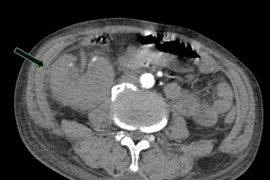

Kỹ thuật TIPS chữa chảy máu tiêu hóa do xơ gan

Kỹ thuật TIPS là một thủ thuật can thiệp nội mạch được sử dụng trong y học để điều trị các biến chứng của tăng áp lực tĩnh mạch cửa do xơ gan...